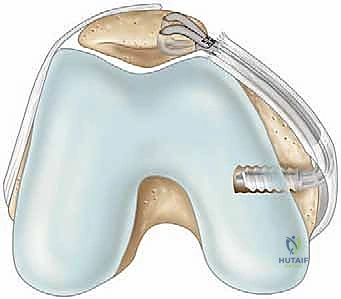

The macroscopic dimensions of the native MPFL are highly consistent across the adult population. It measures approximately 58 mm in length, with an average width of 12 mm and a remarkably thin cross-sectional thickness of roughly 0.44 mm at its midpoint. From its femoral origin, the ligament fans out anteriorly, broadening as it approaches the patella. Its insertion footprint covers the proximal two-thirds of the patella's medial margin, transitioning from a distinct ligamentous band into a broader retinacular expansion. Recognizing this broad patellar footprint is critical; a point-to-point repair using a single anchor often fails to recreate the native biomechanics, necessitating a dual-anchor technique to restore the broad insertion.

Preparation of the patellar bed is a critical step for biologic healing. The native insertion site on the proximal two-thirds of the medial patellar facet is exposed. Using a curette, rongeur, or a high-speed burr, the medial cortical margin is lightly decorticated down to bleeding cancellous bone.

This bleeding bed provides the necessary marrow-derived mesenchymal stem cells and growth factors to facilitate robust ligament-to-bone healing. Two suture anchors (typically 4.75 mm or smaller, biocomposite or PEEK) double-loaded with ultra-high-molecular-weight polyethylene (UHMWPE) sutures are then placed into the decorticated patellar margin. The anchors are spaced appropriately (one proximal, one distal) to recreate the broad native footprint.

The sutures are then passed through the mobilized MPFL stump. A secure, tissue-gripping stitch configuration is mandatory to prevent pull-through. A Krackow stitch or a locking Mason-Allen configuration is placed using the limbs from both anchors, effectively grasping the robust fibrous tissue of the MPFL and the overlying VMO fascia.

The critical moment of the procedure is tensioning. The knee is placed in 30 to 40 degrees of flexion, the point at which the patella should be fully engaged within the trochlear groove. The sutures are drawn tight, advancing the MPFL stump directly onto the decorticated bleeding bone bed. The surgeon must manually assess patellar tracking and lateral translation. The goal is to restore a firm endpoint with 1 to 2 quadrants of lateral glide. Overtensioning must be strictly avoided; the MPFL is a check-rein, not a medializing tether. Once the ideal tension is achieved, the knots are tied securely. The knee is then cycled through a full range of motion to ensure the repair is isometric, does not capture the patella in extension, and maintains stability in flexion.